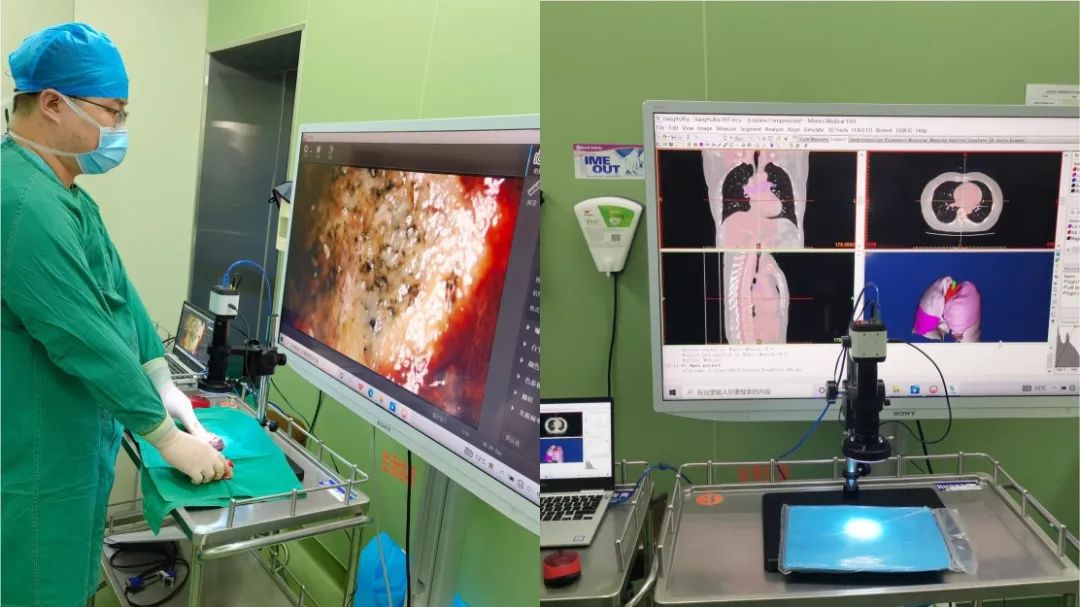

将平面的影像学检查图像重建成3D数字模型

将平面的影像学检查图像重建成3D数字模型DBL帝国网站管理系统